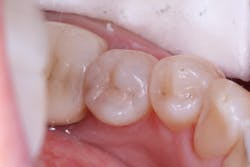

The first case demonstrates a molar with the often-typical A1/B1 shade. It required an occlusal restoration. Following local anesthesia, a DryShield isolation device was placed intraorally. The cavity was accessed and cleaned (figure 1). After rinsing and gentle drying of the dentin, Tokuyama Universal Bond (Tokuyama Dental America), an eighth-generation bonding agent, was applied and dried, without the need for light curing. The Omnichroma composite was built up and cured in 2 mm increments until the tooth was fully restored (figure 2). Note that prior to curing, Omnichroma will appear opaque white. Then, following curing, it immediately blends into the surrounding tooth structure. The occlusion was adjusted, and the composite and surrounding enamel was polished.